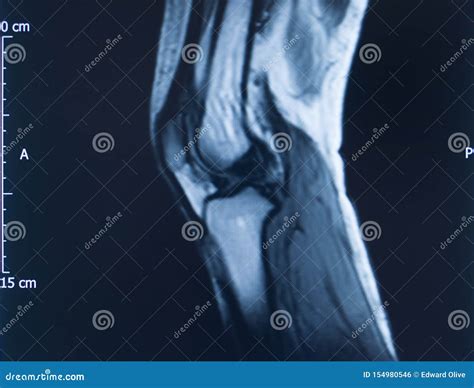

Diagnosing an MCL Tear with an MRI

An Mcl Tear Mri is a non-invasive imaging technique that provides detailed images of the knee joint. MRI uses magnetic fields and radio waves to create cross-sectional images of the body’s internal structures. This allows healthcare professionals to visualize the MCL and other soft tissues in the knee, identifying any tears or damage.

During an *Mcl Tear Mri*, the patient lies on a table that slides into a large, cylindrical machine. The procedure is painless and typically takes about 30-60 minutes. The MRI machine captures multiple images from different angles, providing a comprehensive view of the knee joint.